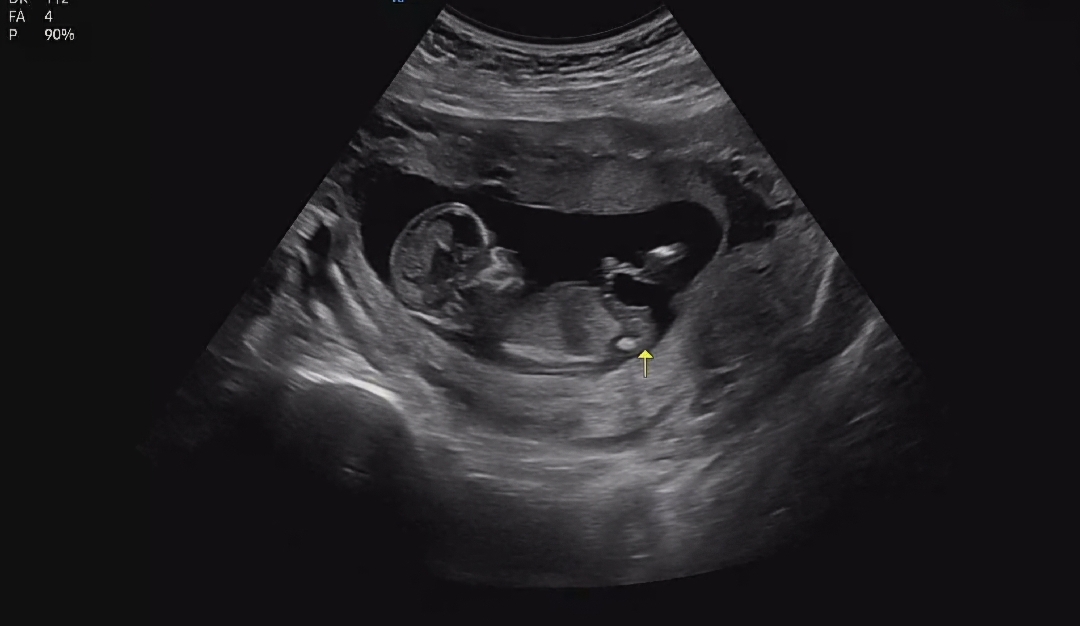

각도법 질문!!!

12주 3일이예요!